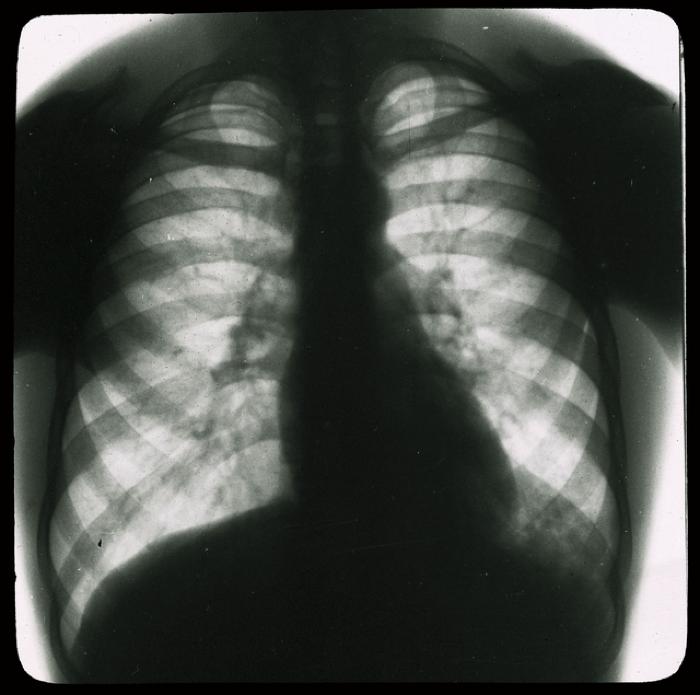

Document médical, radiographie de poumons d'hommes.